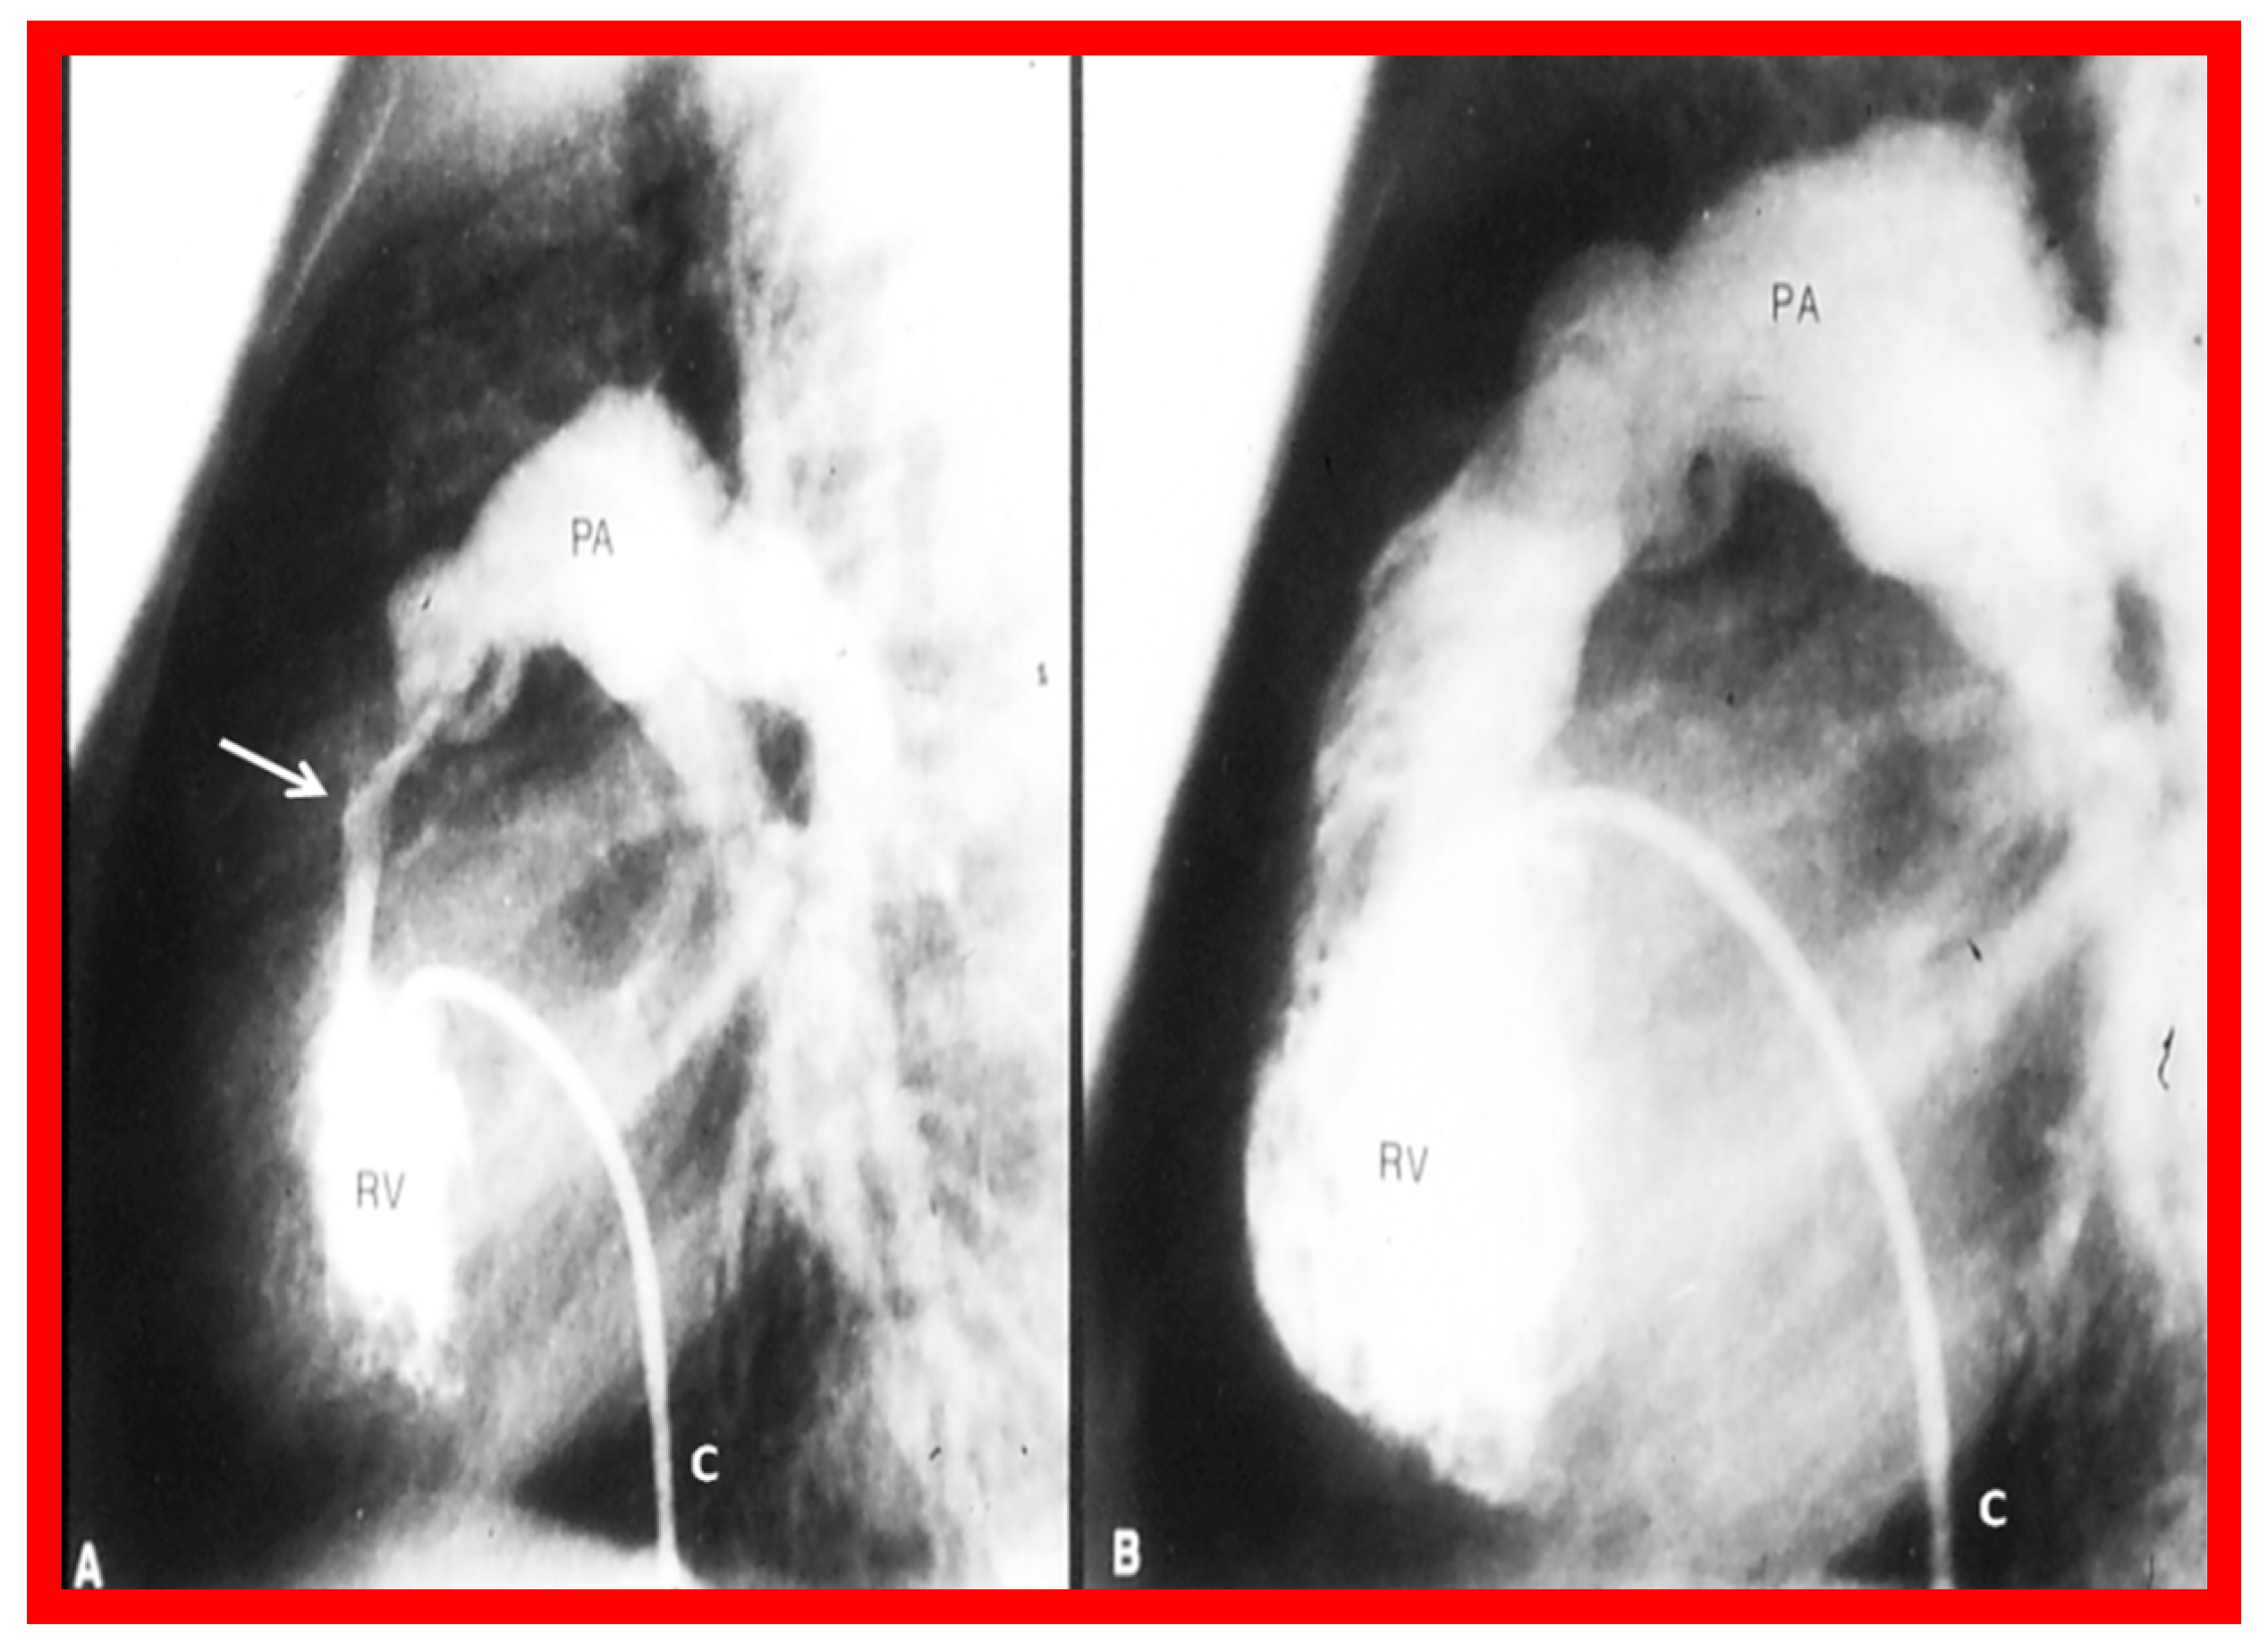

Figure 2. Selected cine frames from right ventricular (RV) angiogram in lateral view, showing severe infundibular stenosis (arrow) (A) immediately after balloon pulmonary valvuloplasty. Note the wide-open right ventricular outflow tract (B) at cardiac catheterization 10 months after balloon valvuloplasty. The peak-to-peak pulmonary valvar pressure gradient at follow-up catheterization was 20 mmHg; there was no infundibular gradient. C, catheter; PA, pulmonary artery. Reproduced from Reference [4].

Figure 2 and Figure 3 demonstrate instances of RV infundibular stenosis as seen on RV angiogram (Figure 2A) and on Doppler study (Figure 3B [middle panel). Ten percent children (six of 62) were administered propranolol either during or following BPV to lessen the RV systolic pressure and to alleviate the RV infundibular stenosis acutely [2,3].

At mid-term follow-up, the RV infundibular stenosis either completely resolved or its magnitude further reduced (Figure 1, Figure 2B and Figure 3C). At the time of the ending of this investigation [2], no patient needed surgery. However, at long-term follow-up [5], three (4%) of 80 patients needed surgery to alleviate fixed RV infundibular obstruction, months, or years after initial BPV.